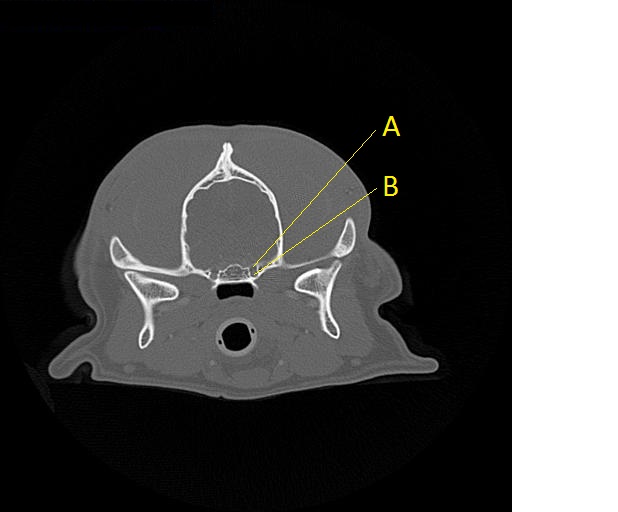

Q. Identify the structures labeled below:

A. round foramen

B. alar canal